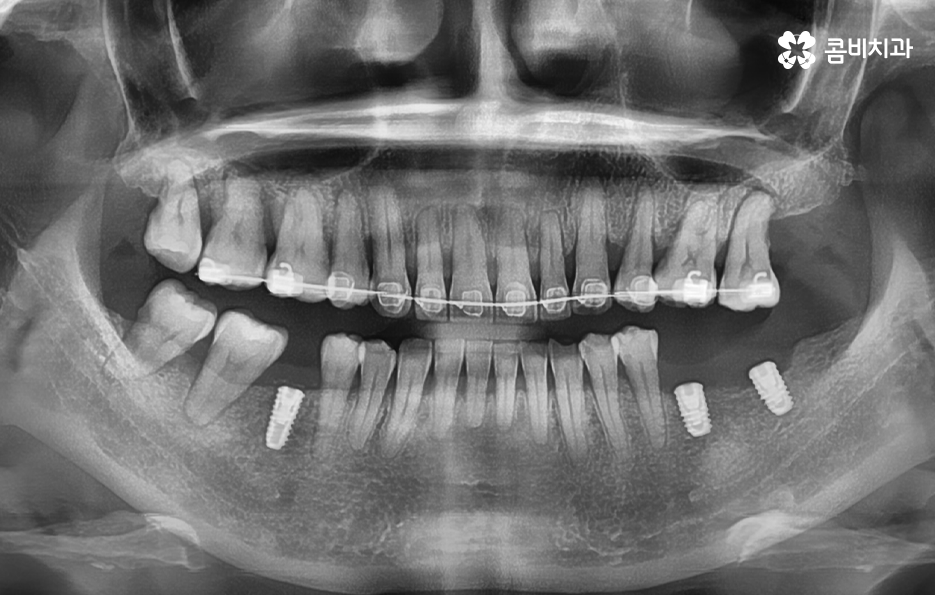

오늘 보시는 포스팅에서의 치료 과정도 어금니에 임플란트가 필요한 상태에서 윗니를 보시면 윗니가 다소 벌어진 것을 확인할 수 있는데요. 교정 하면 보통 전체교정을 떠올리게 되긴 하지만 경우에 따라서는 치열이 전체적으로 가지런한 편인데 앞니가 살짝 벌어진 경우나 어금니만 다소 벌어진 경우도 있을 거예요

이러한 경우에는 부분교정을 통해서 다소 개선이 필요한 치열을 가지런하게 만들고 가지런해진 치열과 교합 상태에 적합한 임플란트 치료 계획을 세워서 치아의 심미성과 기능적인 부분, 얼굴과의 조화를 종합적으로 고려하여 좋은 결과를 얻을 수 있어요

임플란트를 이미 한 상태에서 교정을 계획하는 경우에 대해 설명드리면 일반적으로 치열 위주로만 가지런하게 만들기 위한 치아교정은 임플란트가 크게 방해되지 않는 경우가 대부분이며 이미 치열이 삐뚠 상태에서 임플란트를 하셨던 경우에도 큰 문제가 아닌 경우가 더 많이 있는데요

임플란트를 제외한 자연치아를 우선적으로 치아교정을 하고 임플란트를 한 부위의 보철물은 새롭게 제작하거나 약간의 보철물 조정을 통해서 치료가 가능할 수 있어요

임플란트는 잇몸 뼈에 고정이 되어 있기 때문에 돌출입 교정과 같이 치아의 이동이 많은 경우에는 어렵지 않을까 생각하시는 분들도 많을 거예요. 임플란트를 한 상태에서 돌출입 교정과 같은 치료를 한다고 가정할 때 어금니에 임플란트를 한 경우에는 임플란트를 오히려 고정원으로 써서 앞니를 안으로 당기는데 활용할 수 있어요